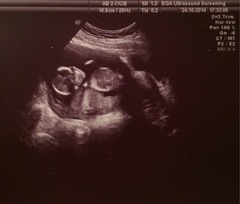

Misty my flu jab made my arm ache for about 36 hours. Here are my pics, baby is hiding behind the placenta (I think) in the second one but has its hand up in the middle of the picture waving hello, and the head and other hand are on the left side.

April 2015 #4 - time to start glowing and growing